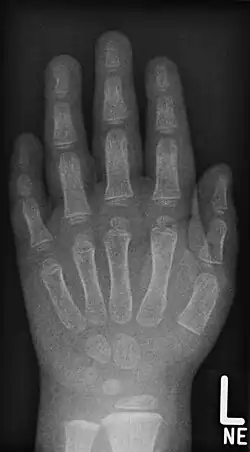

- Röntgenaufnahmen der Handknochen von Kindern unterschiedlichen Alters

Junge, 5 Jahre -